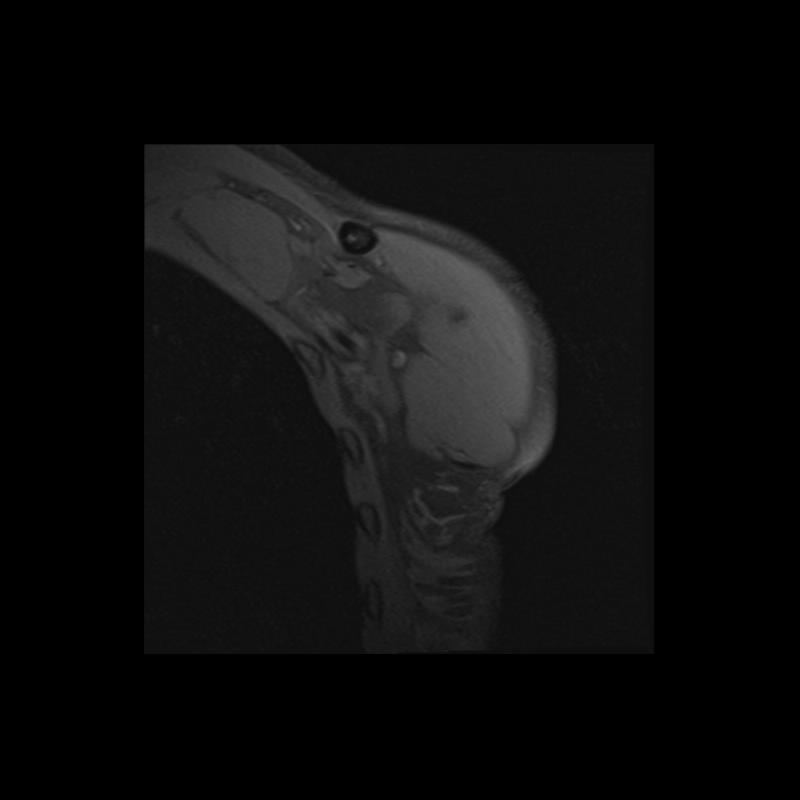

Shoulder MRI Anatomy